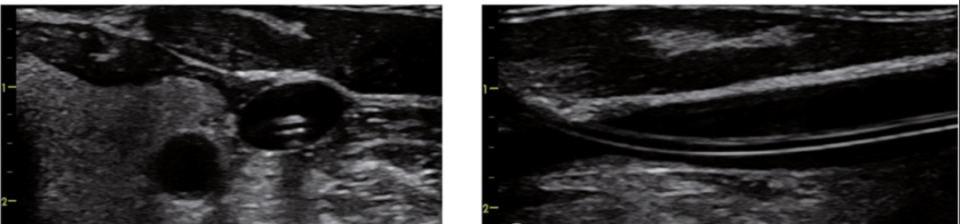

①加压法

由于静脉血管缺乏富含弹性纤维的中膜,管壁较薄,相对于伴行的动脉更容易被压闭,因此可以通过探头加压的方式来观察,首先被压闭的是静脉。

第二步 判断静脉是否通畅

通过轻压探头的手法来了解静脉能否完全被压闭,同时使用彩色多普勒成像和频谱多普勒测量来再次确认静脉的通畅性,排除静脉血栓,并量化血流量。